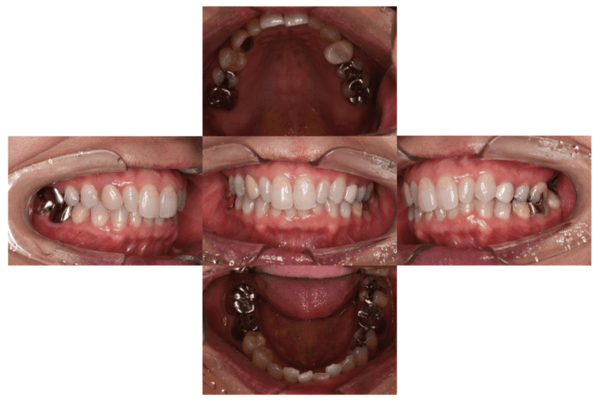

2021.4.3 定期検診時

この時はまだ症状がなかった

しかし歯は縦に割れており、いつ痛みが出てもおかしくないような状態であることは説明していた。

2022.1.15 根尖性歯周炎の急性化

疼痛ありで急患来院。

前々から爆弾抱えているような物で、何かあったら抜歯と伝えていた部位。以前よりクラウンマージン下で歯根縦破折であったが、症状なしで経過観察をおこなっていた。

抜歯予定とし、アモキシシリンとロキソニンを処方した。

2022.2.5 抜歯後の消毒

口腔内写真

CT画像

骨の状態はそこまで悪くないが、欠損が大きい。